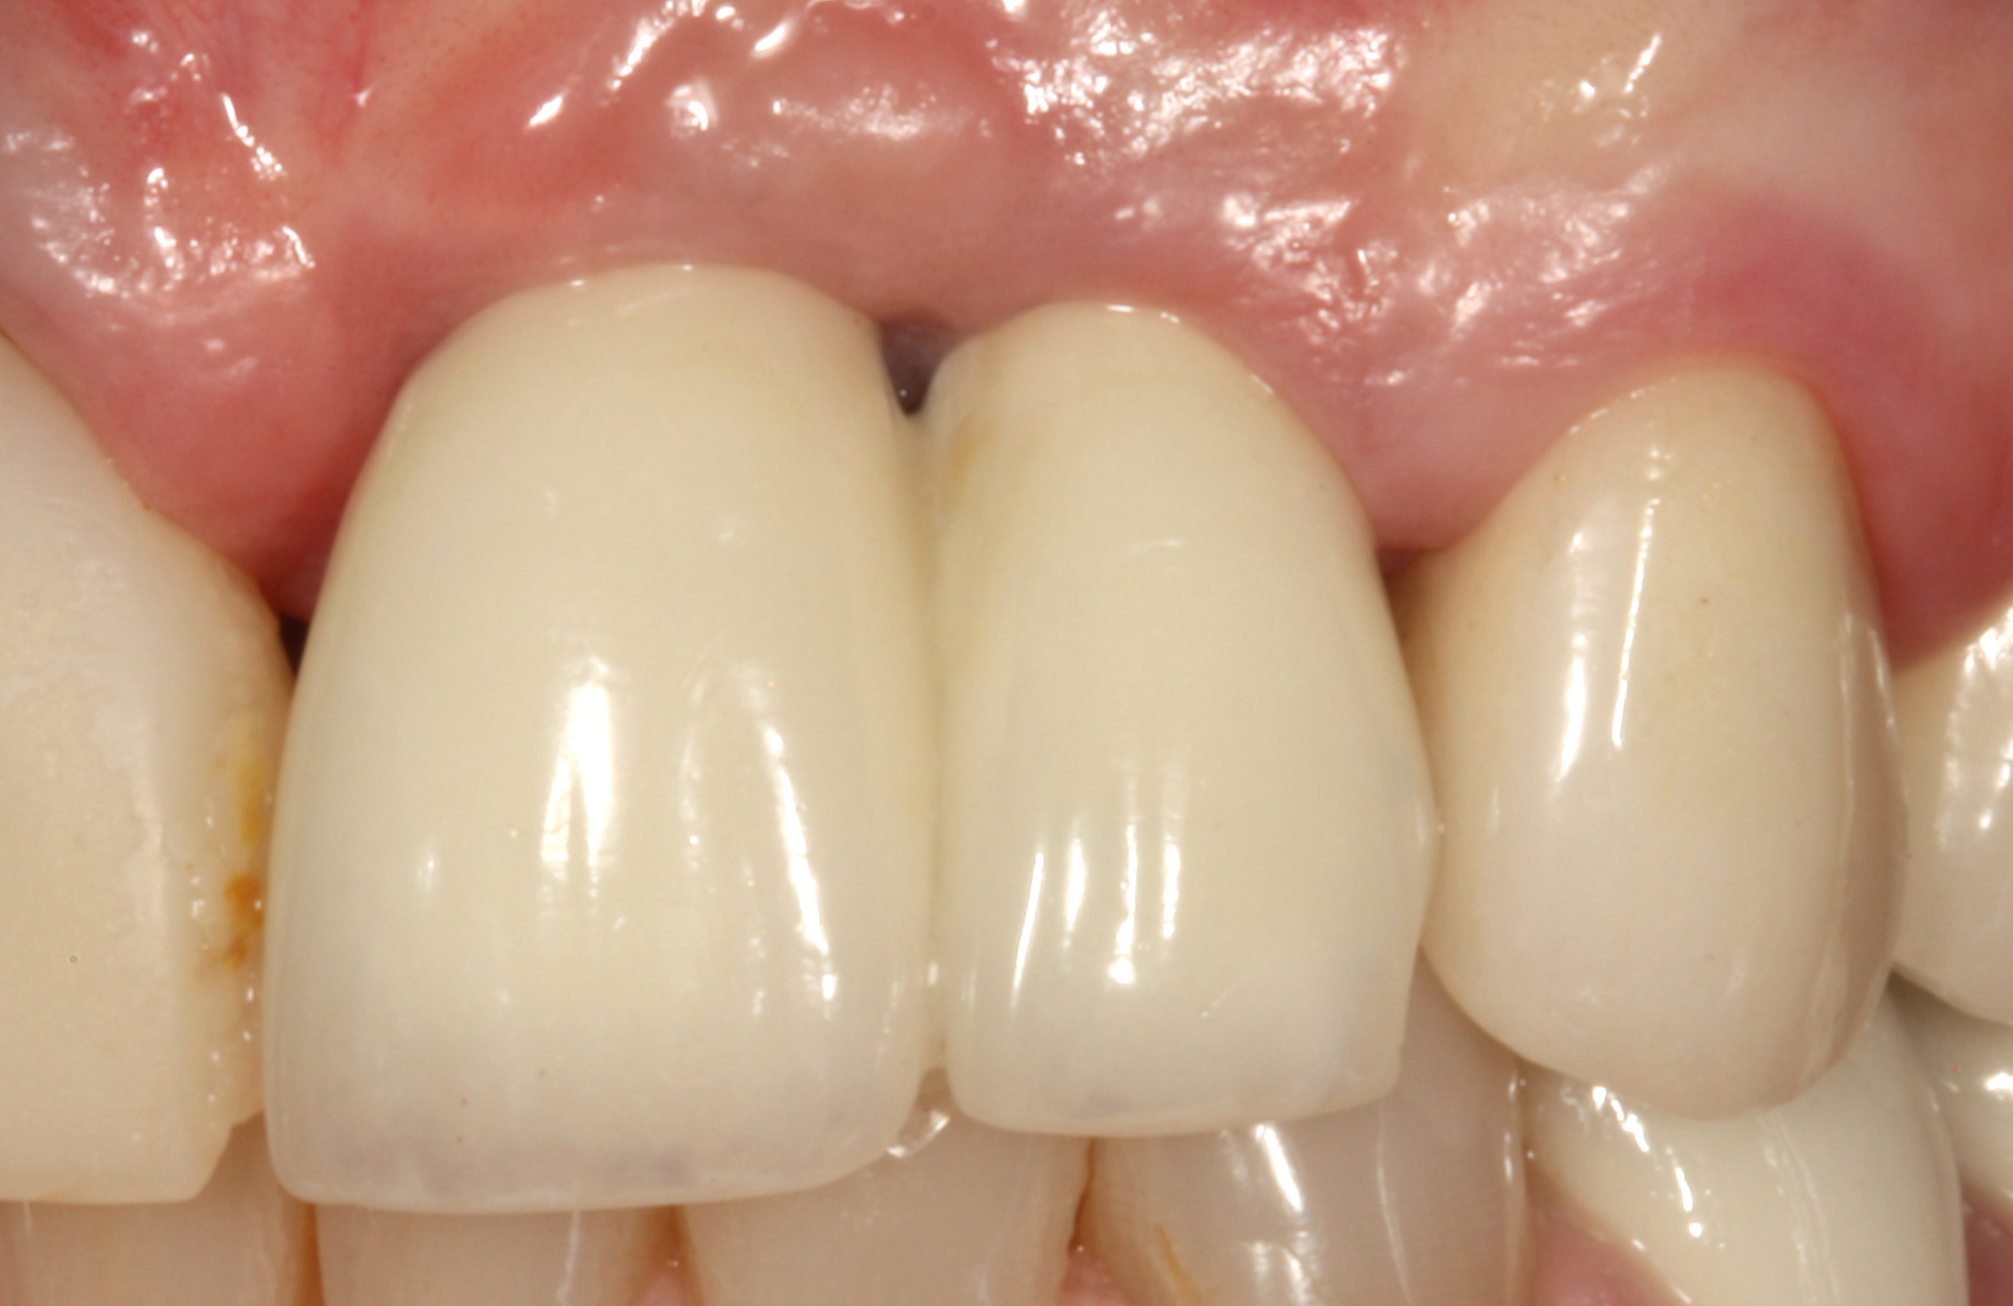

Fig 45. The definitive crown tooth No. 26 seated in place and provisionally cemented. The recession defect was eliminated with the removal and replacement of a new implant in the proper position.

Figure 45